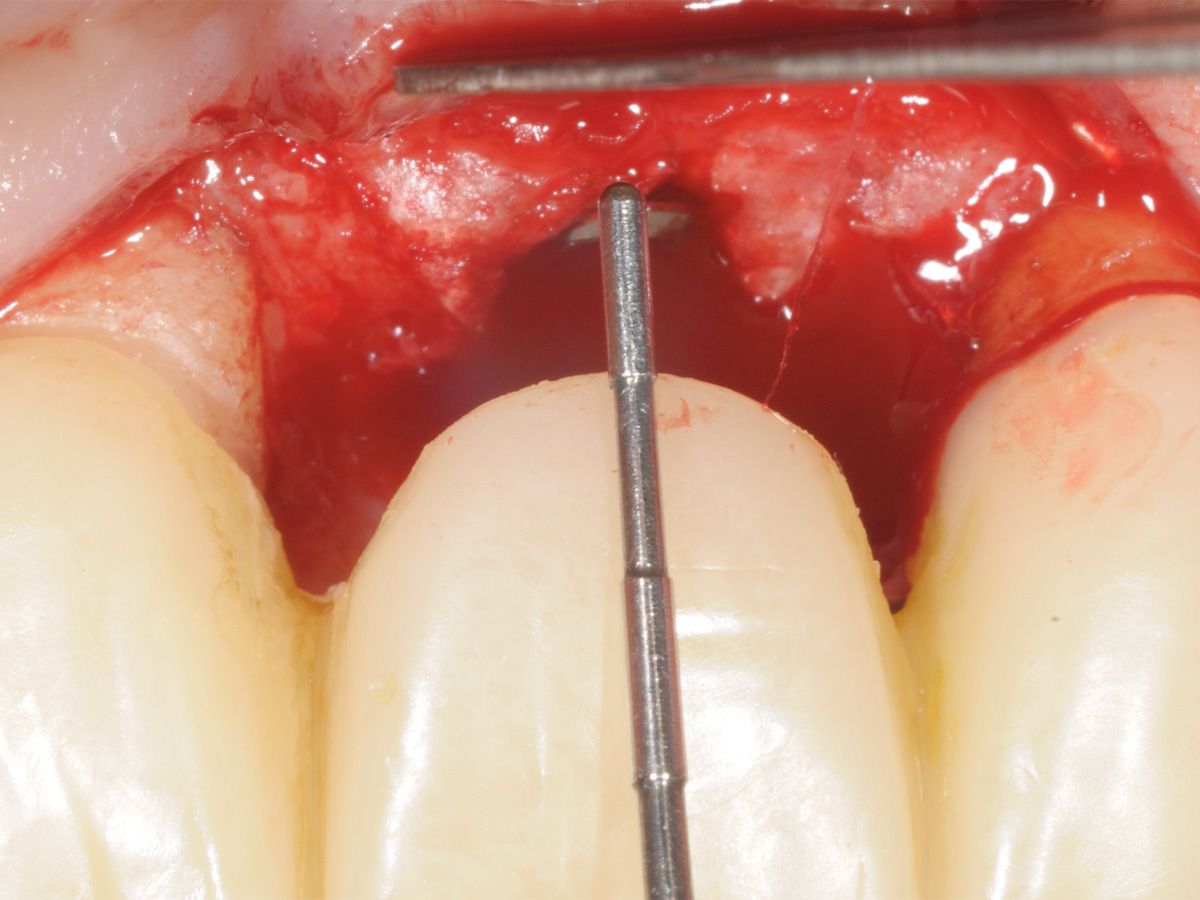

Abbildung 14

Freilegung mittels modifiziertem Rolllappen.